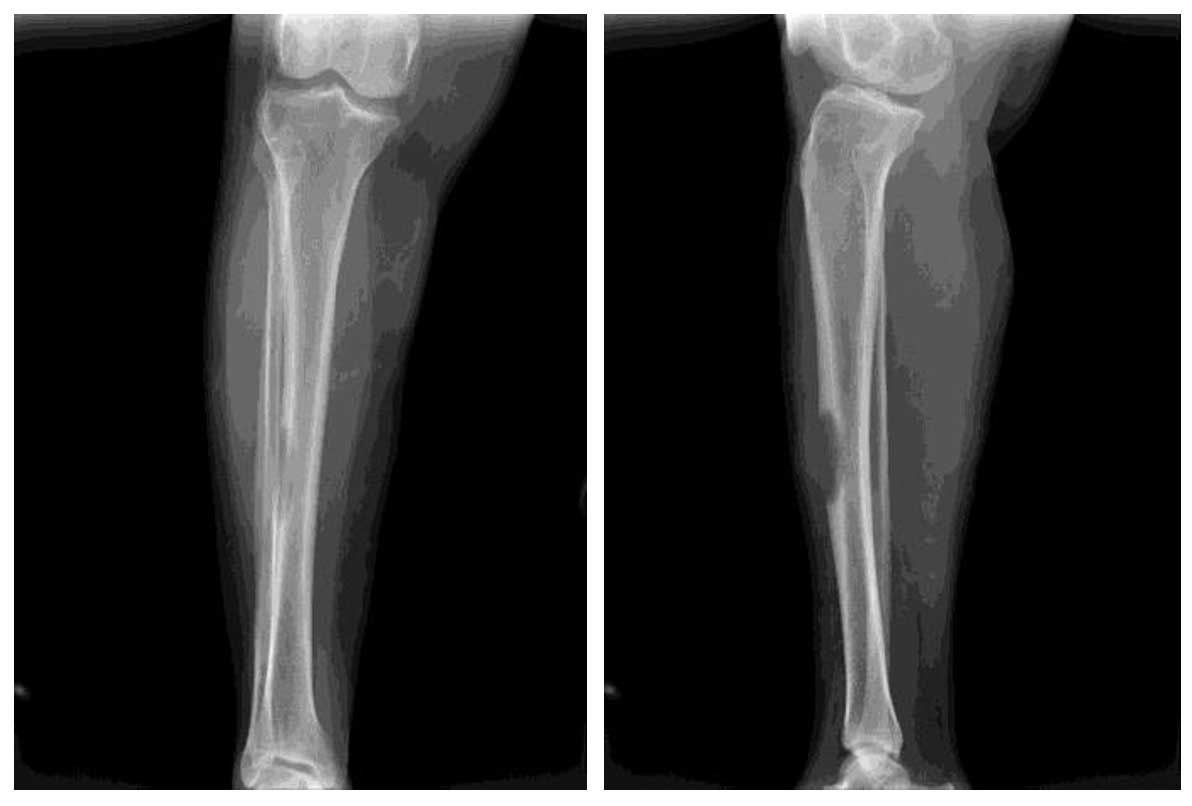

Ameliyat Öncesi: Röntgende kaval kemiği orta kısmında yeniklik ve harabiyetin neden olduğu kırık riski görünmekte.